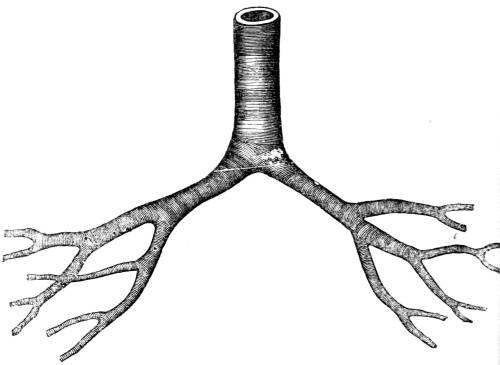

View of the trachea, showing, first, the division of the

tube into the right and left bronchus, and the subdivision

of the bronchi into the bronchial tubes; and secondly, the

membranous and cartilaginous tissues of which the organ

is composed.

364. The second portion of the windpipe termed

the trachea (fig. CXXXV. 2), commences at the

under part of the larynx (fig. CXXXV. 1), and extends

as far as the third dorsal vertebra, opposite43

to which it divides into two branches which

are termed the bronchi (fig. CXXXV. 3, 4, and

CXXXVII. ). One of these branches, called the

right bronchus, goes to the right lung; the other

branch, called the left bronchus, goes to the left

lung (fig. CXXXV. 3, 4).